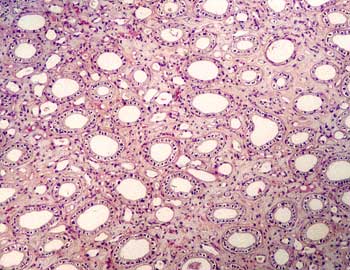

XII-2 Riñón (Hematoxilina-eosina) |

Visión

general: A pequeños aumentos el análisis de la

sección del parénquima renal permite diferenciar una zona

cortical rica en estructuras glomerulares y tubulares y un área

medular constituida fundamentalmente por túbulos renales cortados

longitudinal y transversalmente.

específica: En la zona cortical se visualizan los glomérulos

con el ovillo vascular, la cápsula de Bowman y el mesangio intraglomerular.

Entre los distintos glomérulos observamos secciones longitudinales

y transversales de los túbulos contorneados proximales (TCP)

y distales (TCD). Los TCP aparecen tapizados por células prismáticas

con superficie irregular confiriéndoles la apariencia de que

la luz está ocupada mientras que los TCD aparecen tapizados por

células más bajas y con una luz óptimamente vacía.

Intercalados aparecen estructuras vasculares y el intersticio de sostén

escaso. En la médula observamos grandes túbulos colectores

(TC) acompañados de otras estructuras ductales más pequeñas

correspondientes a las asas de Henle. Los TC presentan un epitelio prismático

de células claras y oscuras y las asas de Henle están

tapizadas por células aplanadas en los segmentos finos y células

cúbicas en los porciones gruesas. El intersticio renal medular

es más abundante y contiene una gran riqueza de vasos sanguíneos.

- Análisis

histológico diferencial de las porciones cortical y medular

del parénquima renal.

- Estudio

detallado de los componentes glomerular, tubular, vascular e intersticial.